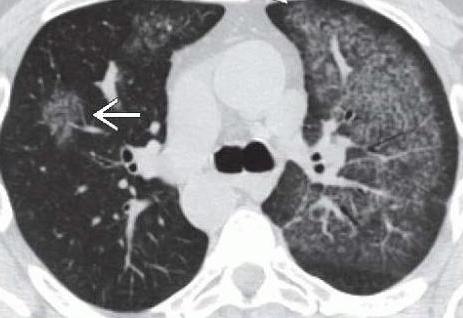

К наиболее часто встречающимся легочным патологиям, которые осложняются кровотечением, относят туберкулез, рак и бронхоэктатическую болезнь. Все эти недуги очень опасны и требуют длительного лечения в специализированных учреждениях. Легочное кровотечение свидетельствует о прогрессирующем кавернозном туберкулезе. Зачастую оно возникает на фоне приступа кашля.

При раке легкого кровотечение свидетельствует о распаде опухоли и повреждении сосудов. Остановить его бывает очень сложно. Особо опасно профузное кровотечение, при котором выделяется 500 мл биологической жидкости. Подобный симптом может закончиться летальным исходом. Помимо того что идет кровь изо рта, пациенты жалуются на затруднение дыхания, кашель, потерю веса.

Кровотечение при раке легких: особенности

Рак легкого считается одной из самых распространенных онкологических патологий среди мужчин. В большинстве случаев он развивается на фоне хронических воспалительных болезней дыхательной системы. Главным фактором риска считается злоупотребление табакокурением на протяжении долгих лет. Источником кровотечения при раке являются поврежденные сосуды или сама опухоль, находящаяся в фазе распада.

Признаками заболевания является длительный сухой кашель, не поддающийся лечению. Через несколько месяцев присоединяется кровохарканье. Помимо этого отмечается лихорадка, выраженная слабость, одышка и потеря веса. Кровотечение может иметь различный объем: от малого (50-100 мл) до профузного (более 0,5 литра). В большинстве случаев оно сопровождается кашлем. При этом имеется высокий риск аспирации и развития геморрагического шока.